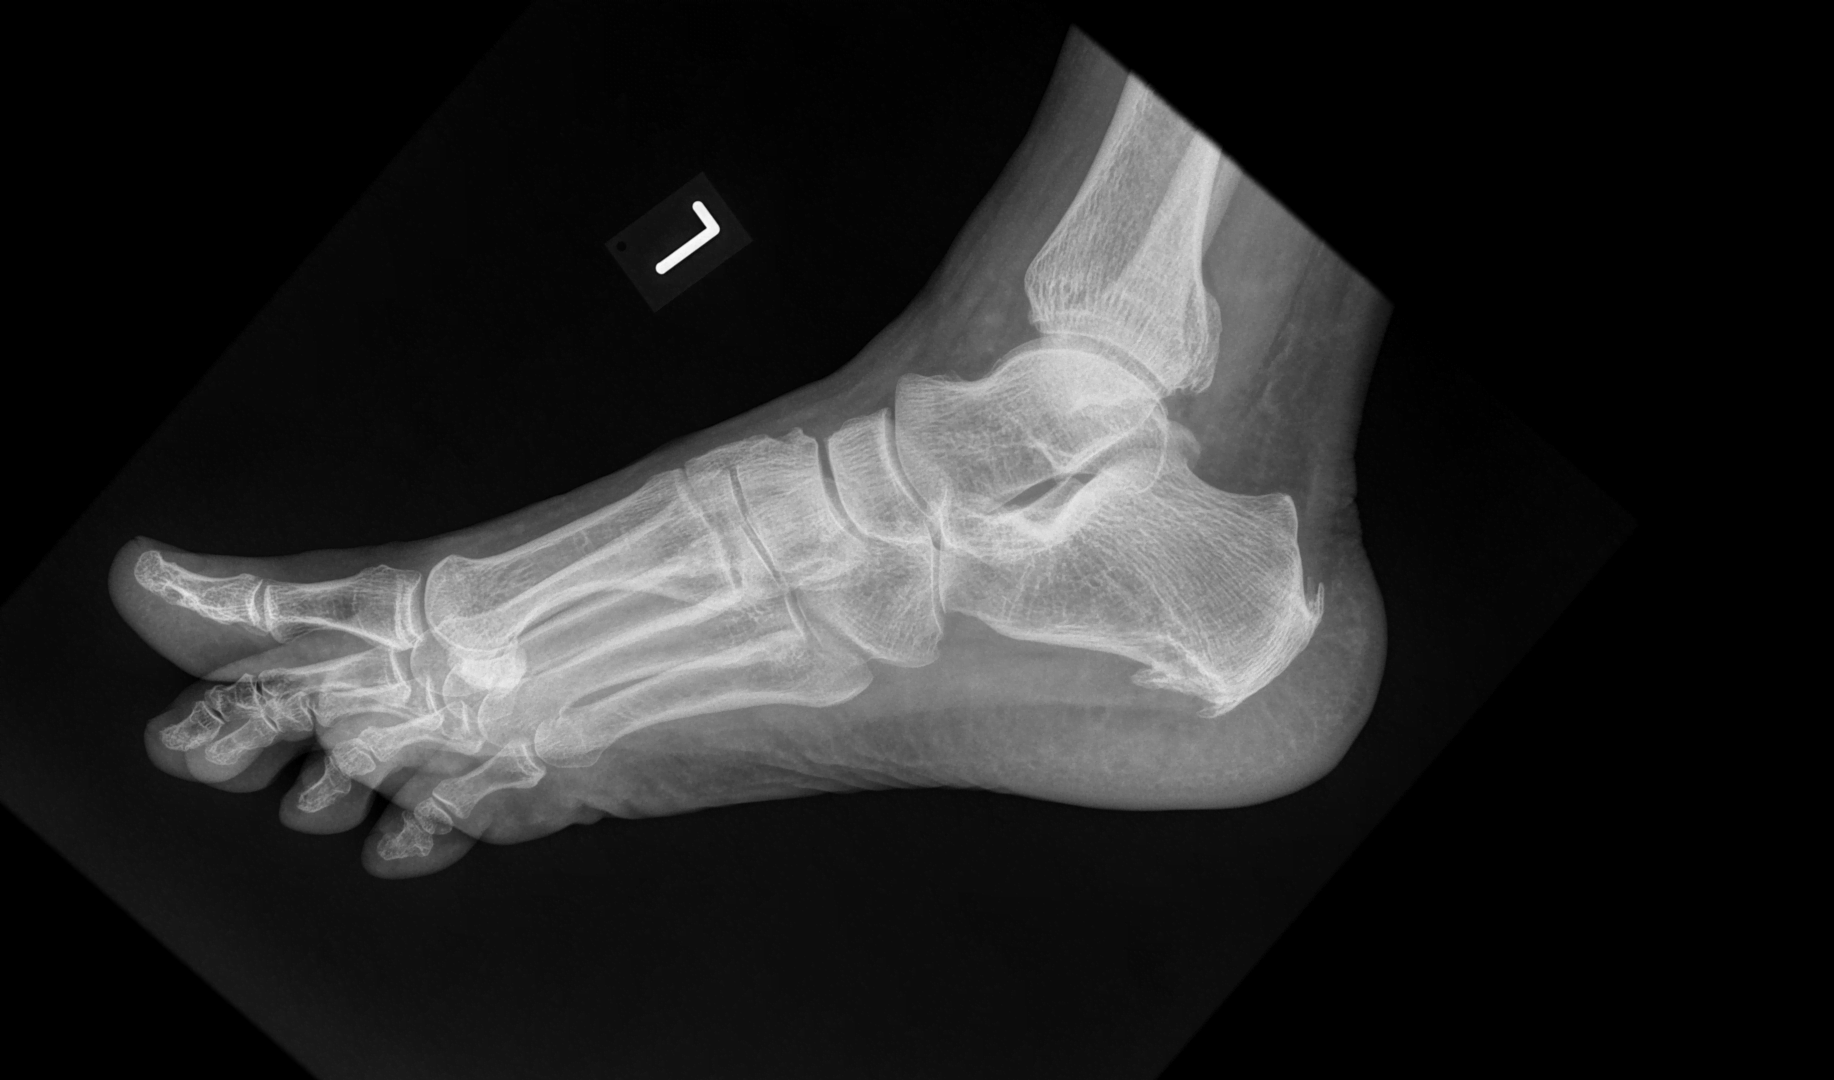

Doznałeś urazu stopy? Masz stan zapalny np. rozcięgna podeszwowego? Potrzebna Ci rehabilitacja stopy. Warszawa, Twardowska 3 – to w tym miejscu mieści się klinika Body Move. U nas możesz liczyć na kompleksową rehabilitację stopy, wynikającą zarówno z urazów mechanicznych, deformacji jak i zmian zwyrodnieniowych.

Rehabilitację stopy wykonujemy jako leczenie zachowawcze, jak również w sytuacji, gdy jest ona konieczna po operacji stopy. Cierpisz na ostrogę piętową dolną lub górną? Masz problemy ze ścięgnem Achillesa lub rozcięgnem podeszwowym? A może Twoim problemem są haluksy, płaskostopie podłużne albo płaskostopie poprzeczne? Na tych wszystkich schorzeniach doskonale się znamy. Niemal każdego zgłaszają się do nas pacjenci, których interesuje właśnie rehabilitacja stopy. W Warszawie nie brakuje gabinetów rehabilitacji, wybór specjalistów jest ogromny, jednak mało kto ma tak duże doświadczenie w tym zakresie, jak zespół fizjoterapeutów Body Move. To osoby po specjalistycznych studiach i licznych szkoleniach. Na bieżąco podnoszą swoje kwalifikacje, śledzą nowinki z branży i testują nowoczesne techniki, a wszystko po to, by zapewnić jak najlepsze wsparcie pacjentów. Są przy tym bardzo serdeczni, empatyczni i wyrozumiali. Dlatego rehabilitacja z nimi zawsze przebiega w miłej atmosferze, co wpływa też pozytywnie na samopoczucie naszych pacjentów. Chciałbyś się o tym przekonać osobiście? Zapisz się już dziś na rehabilitację stopy w naszej klinice. Na pewno nie pożałujesz!

Rehabilitacja stopy polega na przywróceniu pełnego zakresu ruchów w stopie, wyleczeniu stanu zapalnego i zniesieniu dolegliwości bólowych. Jak to robimy w Body Move? Na bazie naszych wieloletnich doświadczeń i nowoczesnych metod terapeutycznych, przy rehabilitacji stopy stosujemy techniki terapii manualnej tkanek miękkich i terapii manualnej stawowej. Wykonujemy też kinesiotaping i taping medyczny, jak również suchą igłoterapię, fizykoterapię, a także ćwiczenia rozciągające i wzmacniające dobrane pod konkretnego pacjenta. Prowadzimy analizę biomechaniczną, nie tylko stopy, ale całej kończyny dolnej – wszystko po to, by zminimalizować ryzyko nawrotu dolegliwości.

Naszymi pacjentami są nie tylko zwykli ludzie i osoby amatorsko uprawiający sport. Mamy pod opieką wielu zawodowych sportowców, olimpijczyków dzięki czemu doskonale orientujemy się w najnowocześniejszych technikach rehabilitacyjnych i metodach leczenia. Zapraszamy na rehabilitację stopy w przypadku gdy doskwierają Ci bóle będące pochodną zmian zwyrodnieniowych, bóle przeciążeniowe, czy też naciągnięcia lub naderwania mięśni. Mamy ogromne doświadczenie w rehabilitacji ścięgna Achillesa i rozcięgna podeszwowego. Skutecznie rehabilitujemy takie schorzenia jak ostroga piętowa i choroba Mortona. Leczymy stany zapalne i dolegliwości bólowe związane również z deformacjami: haluksy, płaskostopie poprzecznie i płaskostopie podłużne. W naszej klinice w Warszawie rehabilitację stopy wykonujemy też po złamaniach i pęknięciach – wszystko pod bacznym okiem wykwalifikowanych i sympatycznych fizjoterapeutów.